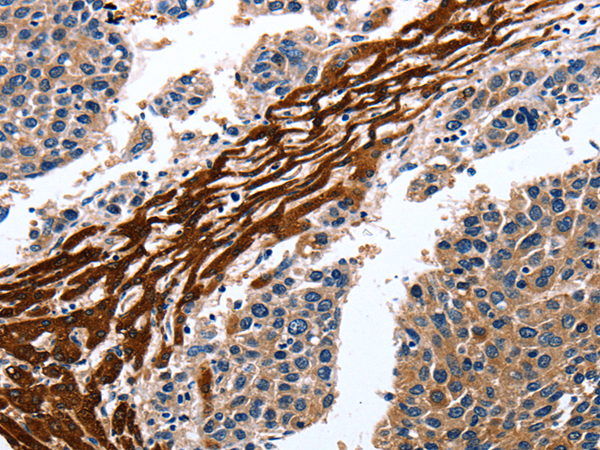

分类: 科研抗体货号: P07246别名: LIT; DCR1; TRID; CD263; TRAILR3; TRAIL-R3; DCR1-TNFR应用: IHC反应种属: Human